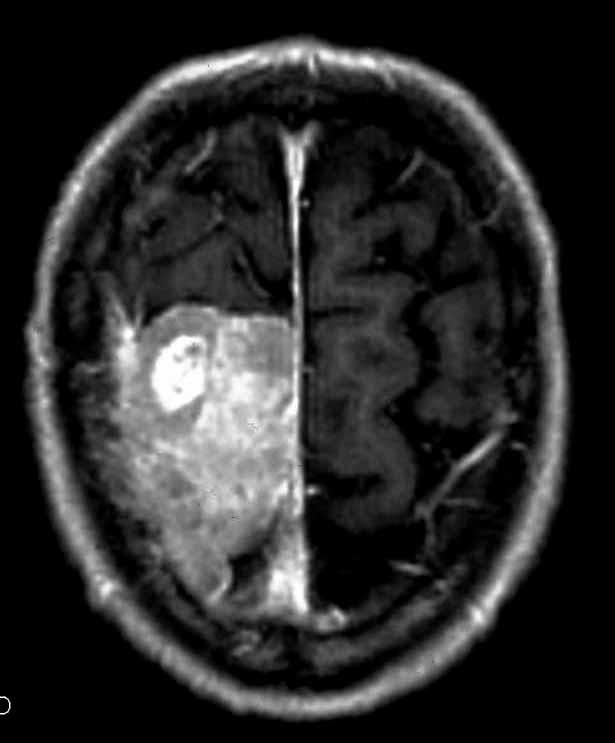

Meningioma |

| Meningioma

con demolizione-ricostruzione della teca cranica in un unico tempo

con tecnica microchirurgica e neuronavigazione. |